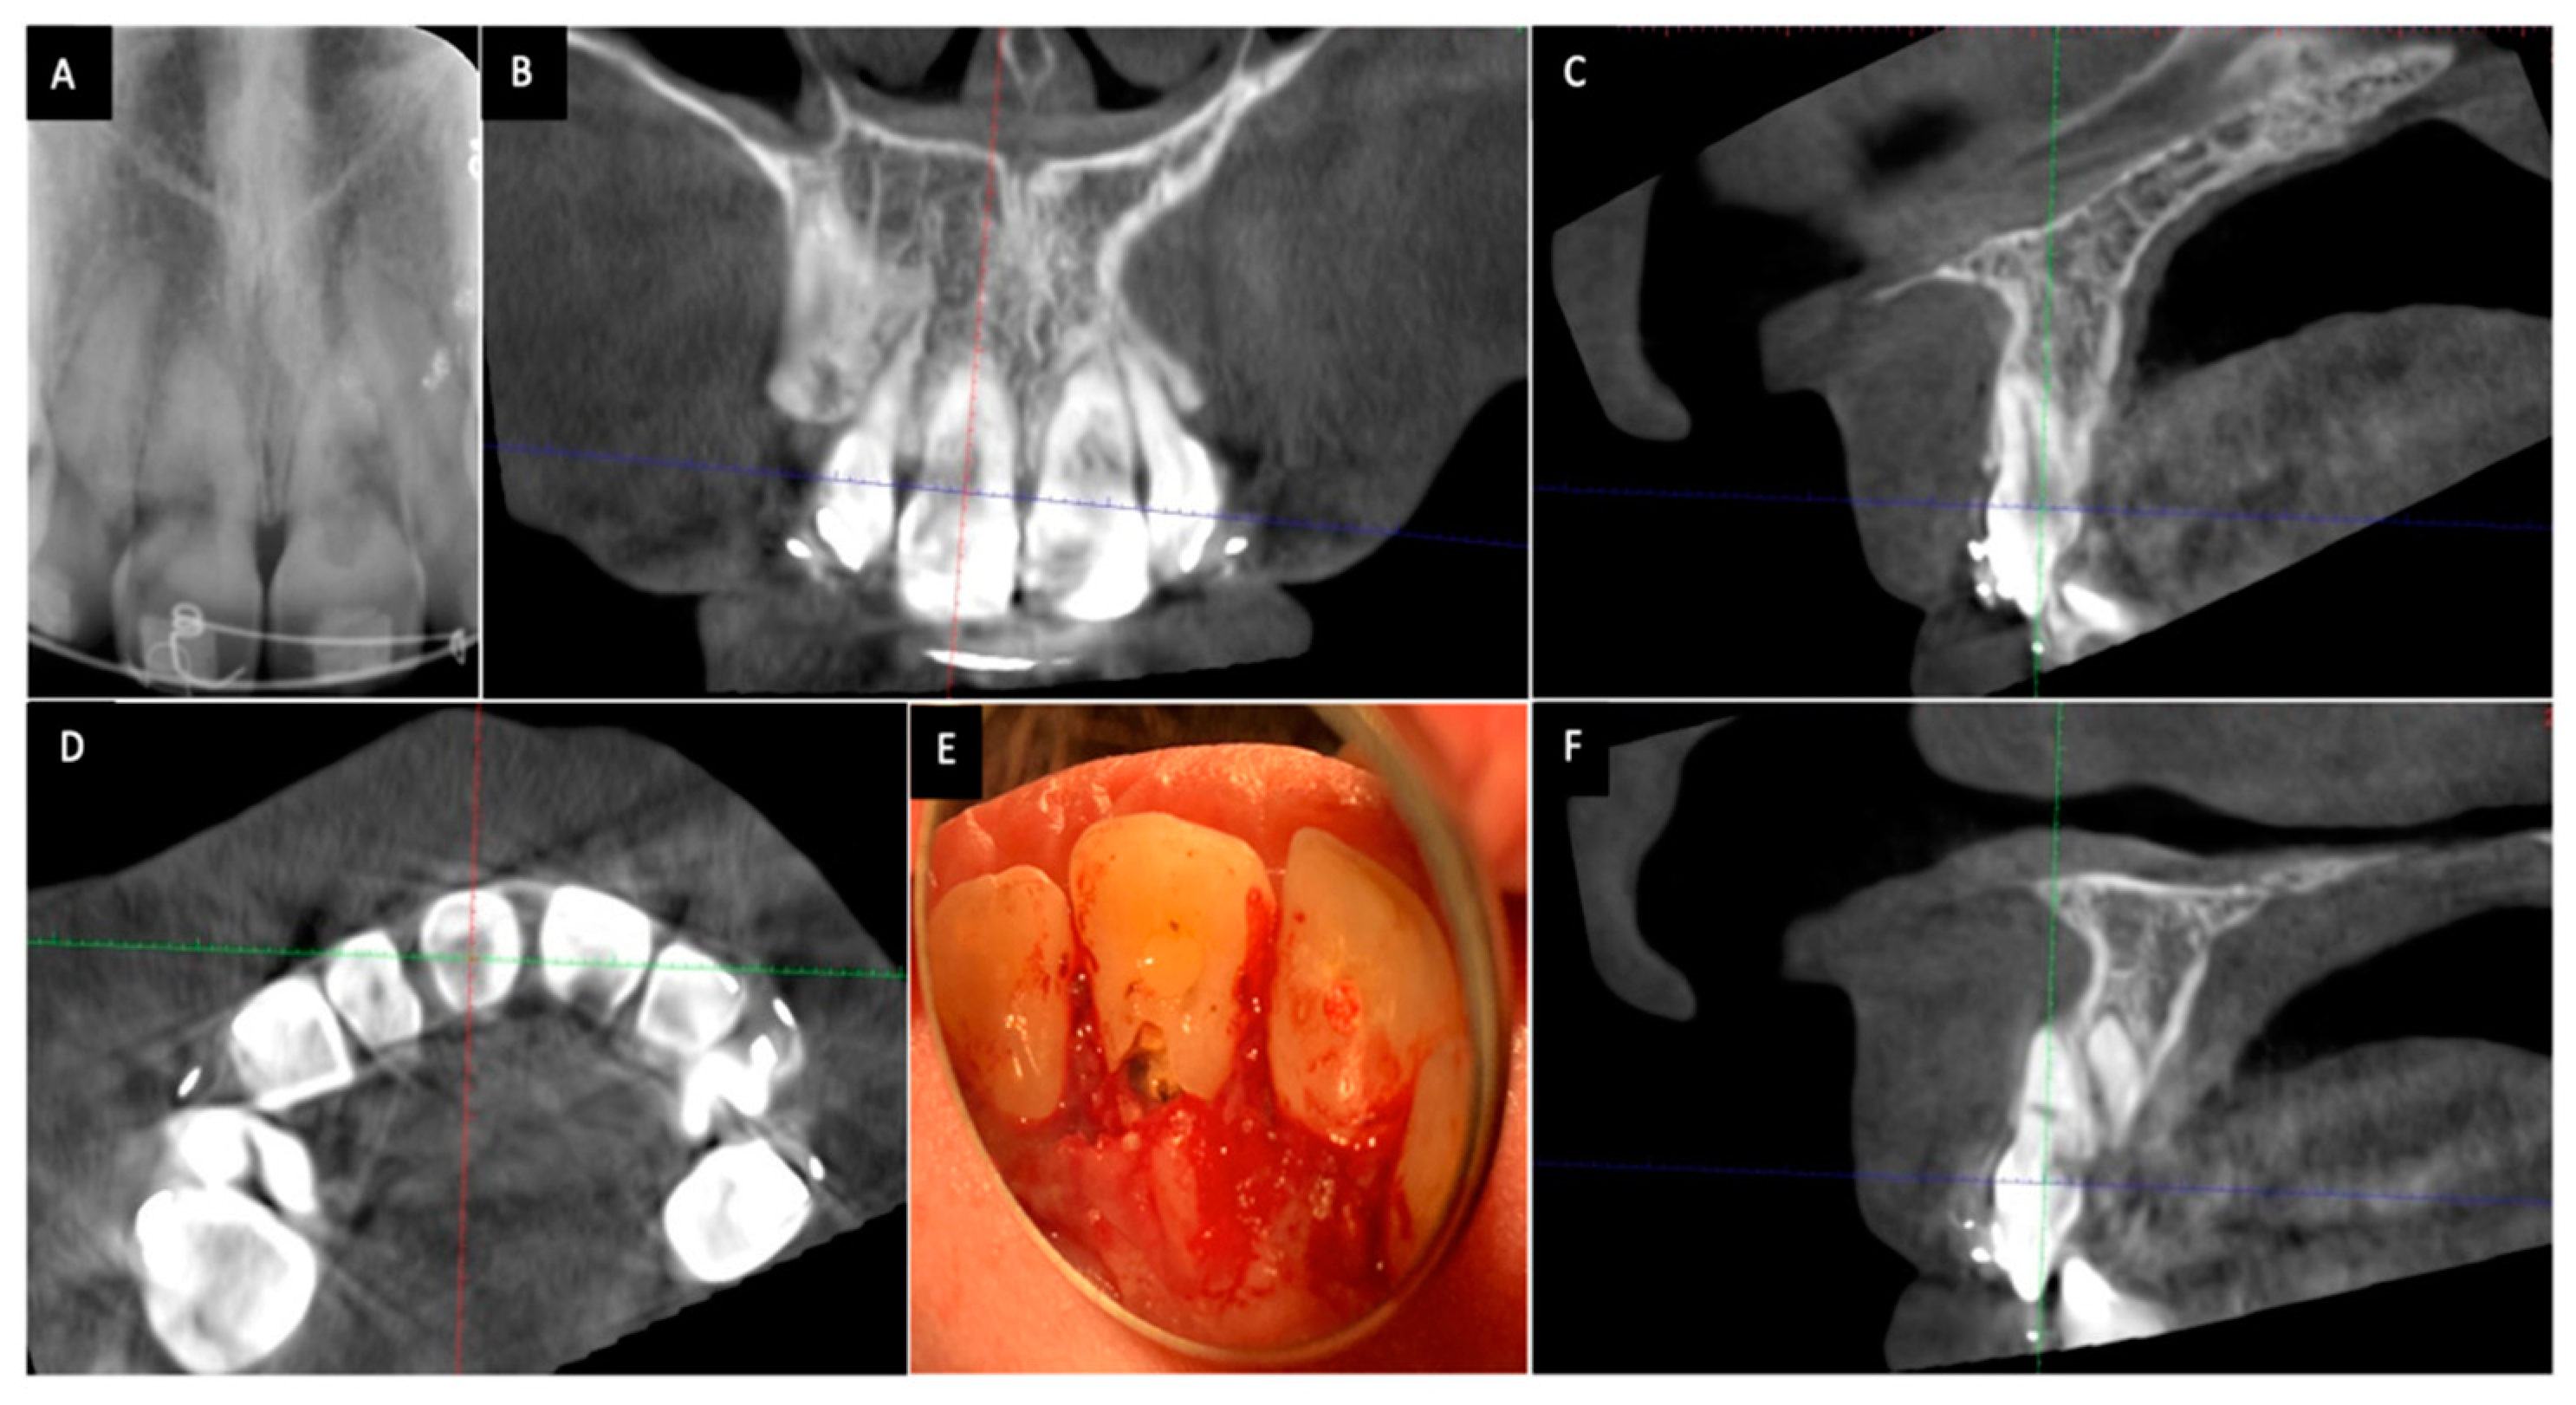

1. فحص السن والتأكد من حالته السنية

قبل البدء بأي إجراء يقوم الطبيب بتقييم شامل للسن. يتضمن ذلك فحصا سريريا وأخذ صور أشعة للتأكد من أن علاج العصب السابق قد تم بشكل جيد وأن الحشوة محكمة الإغلاق عند قمة الجذر ولا يوجد أي التهاب أو خراج حول الجذر. هذه الخطوة حيوية لضمان سلامة الإجراء .

2. فتح بسيط لتجويف السن

تحت عزل تام باستخدام الحاجز المطاطي (Rubber Dam) يقوم الطبيب بإزالة جزء من الحشوة الخلفية للسن للوصول إلى حجرة العصب التي تم تنظيفها سابقا. هذا الفتح يكون محافظا وصغيرا جدا.

3. تنظيف داخلي وتجهيز السن لاستقبال المادة

يتم تنظيف حجرة العصب بعناية لإزالة أي بقايا من مواد الحشو القديمة أو الأنسجة المتحللة التي قد تكون سببا في التصبغ. بعد ذلك يتم وضع طبقة واقية عازلة (Coronal Seal) فوق حشوة قناة الجذر مباشرة مثل مادة الأسمنت الأيونومري الزجاجي. هذا الحاجز ضروري جدا لمنع تسرب مادة التبييض إلى قناة الجذر والأنسجة المحيطة وهو أهم إجراء للوقاية من المضاعفات مثل الامتصاص الجذري.

الخطر الأهم: الامتصاص الجذري الرقبي الخارجي (External Cervical Root Resorption)

هذا هو الخطر الأهم والأكثر جدية المرتبط بالتبييض الداخلي على الرغم من أنه نادر الحدوث مع التقنيات الحديثة. يحدث الامتصاص الجذري عندما تتسرب مادة التبييض (خاصة بيروكسيد الهيدروجين عالي التركيز) من حجرة العصب عبر الأقنية العاجية إلى منطقة عنق السن الخارجية (عند خط اللثة) مما يحفز استجابة التهابية تؤدي إلى تآكل جذر السن . أظهرت المراجعات العلمية أن هذا الخطر يزداد بشكل كبير في الحالات التالية: